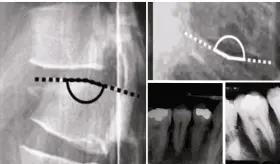

El antecedente de fracturas costales recurrentes por tos y el uso prolongado de omeprazol, un inhibidor de la bomba de protones, son factores que contribuyen a la disminución de la densidad ósea, favoreciendo la osteoporosis.